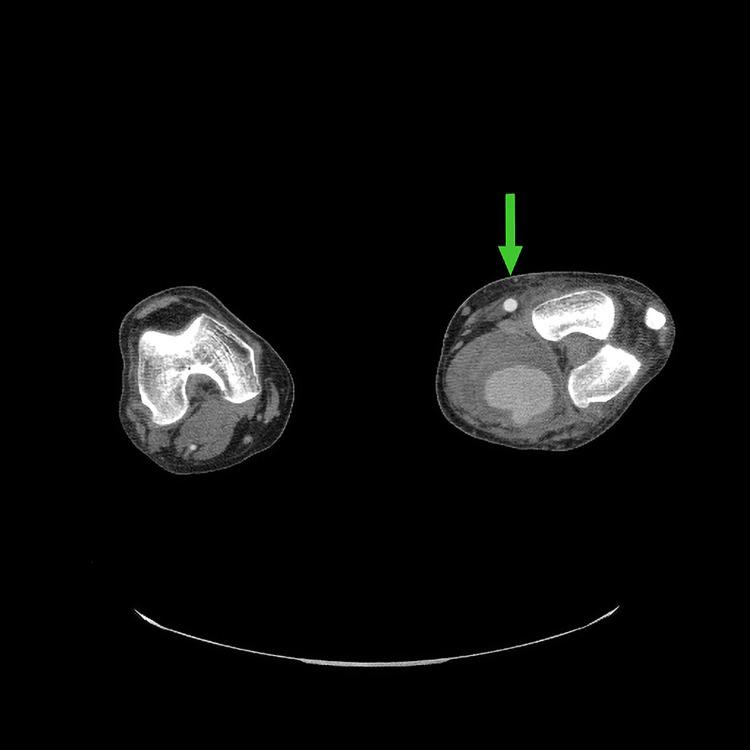

Popliteal artery aneurysms (PAAs) are the most common type of peripheral artery aneurysms. Mycotic aneurysms involving the popliteal artery are quite rare and can occur as either a primary infection or a secondary infection from another site. To our knowledge, there are no previous case reports on mycotic PAA in which was the primary etiologic pathogen. We present the case of a 55-year-old male who presented with complaints of lower extremity pain and swelling, malaise, and low-grade temperatures for two weeks and was found to have a PAA. He underwent left femoral-popliteal bypass grafting with expanded polytetrafluoroethylene (ePTFE) graft and ligation of the aneurysm. On postoperative day 10, he experienced acute swelling and pain in his lower extremity with foot drop and was found to have rapid enlargement of his aneurysm sac on imaging. He was returned to the operating room emergently where he underwent aneurysmectomy via a posterior fossa approach. Cultures and gram staining of the aneurysm sac were consistent with As noted above, this case of mycotic PAA was treated with standard vascular surgical techniques, yet it proceeded to enlarge acutely. PAAs that rapidly expand or rupture after surgical interventions may be a sign of infection.

腘动脉瘤(PAA)是最常见的周围动脉瘤类型。累及腘动脉的感染性动脉瘤非常罕见,可作为原发性感染或来自其他部位的继发性感染出现。据我们所知,以前没有关于以[具体病原体]作为主要病因病原体的感染性PAA的病例报告。我们报告一例55岁男性,他因下肢疼痛、肿胀、全身不适和低热两周前来就诊,被发现患有PAA。他接受了用膨体聚四氟乙烯(ePTFE)移植物进行的左股腘动脉搭桥术和动脉瘤结扎术。术后第10天,他出现下肢急性肿胀和疼痛伴足下垂,影像学检查发现动脉瘤囊迅速增大。他被紧急送回手术室,通过后颅窝入路接受了动脉瘤切除术。动脉瘤囊的培养和革兰氏染色与[具体病原体]一致。如上所述,该例感染性PAA采用标准血管外科技术治疗,但仍急剧增大。手术干预后迅速扩张或破裂的PAA可能是感染的迹象。